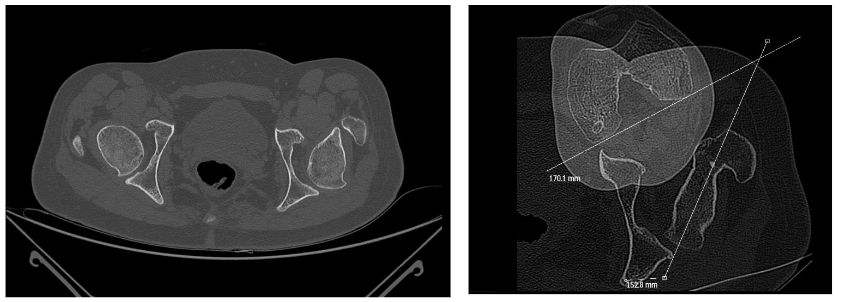

We check the various components which add up internal rotation during gait and correct the torsion of the foot, the tibia, and the femur. We see the cause for an increased femoral anteversion in a lack of spontaneous normal reduction of anteversion and correct it to the midpoint of hip rotation (that external rotation equals internal rotation). The outcome reports are satisfying but not really reliable and long lasting in an individual. Especially if corrected early, anteversion relapses. We thus should consider the femoral anteversion a result of bony adaptation at the forces resulting from daily use, and should evaluate the factors which lead to internal rotation at the hip. We know that toe walking can be one component, midfoot break another, and we see rocking on an internally rotated foot as a further component. If the foot is more than about 30 degrees internally rotated, rocking on this foot twists the foot and indirectly the leg internally until push off. In asymmetric internal rotation as in unilateral cerebral palsy, hip internal rotation is often combined with pelvic retraction on the same side. A common still hypothetical explanation is that the better leg takes the functional lead which would require excellent motor control as the difference must be perceived. Modelling rocking on an equinus foot, however, provides a simple mechanical passive reaction as an explanation. In a patient with sensational and motor control deficits, this second explanation is at least as attractive. The consequence of accepting that anteversion is secondary, is that the causing factors need to be addressed as well when femoral torsion is corrected. An indication for the soundness of this concept is that correcting toe walking into a heel toe gait prevents the development of hip internal rotation deformity.

A second problem arises by focussing on femoral anteversion as the origin: The movement of the hip is normally not limited by bony structures but by ligaments, capsule, and muscles. These tissues adapt faster than bone. If recurrent internal rotation deformity is treated by repetitive derotation osteotomies, there is a risk for uncovering the femoral head on the posterior part.

On the other hand, the forces that act on the proximal femur and shape the anteversion occur not only during walking, but during all activities during the day, including sitting. We do not yet have clear data about these forces. Nevertheless, we should broaden the field of vision of our concept and also include indirect, causal and new factors in our treatment.